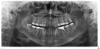

Талина Опубликовано 24 декабря, 2007 Поделиться Опубликовано 24 декабря, 2007 Здравствуйте, посоветуйте, пож-ста. в области 36 зуба появилась шишка, где-то 5-7 мм, зуб леченый (сильно), сам не болит, шишка тоже не болит, обнаружила случайно, никак не беспокоит, пошла к врачу (хирургу), отослал на снимок (прилагаю), потом сказал, что зуб лечить бесполезно, все равно дело кончится удалением, позвал еще 2-х терапевтов, те сказали: "однозначно удалять". Пошла в другую клинику, там тоже сказали надо удалять. Но... удалять жалко, может можно полечить или все-таки бесперспективняк? Что скажете? снимок (переписка по поводу снимка удалена, дабы не засорять тему) Ссылка на комментарий

Dr. Smile Опубликовано 24 декабря, 2007 Поделиться Опубликовано 24 декабря, 2007 Согласен с Анной. Перспективы у зуба есть, при условии что доктору удастся извлечь штифт и пройти каналы. Ссылка на комментарий

annda Опубликовано 24 декабря, 2007 Поделиться Опубликовано 24 декабря, 2007 Нечто у Вас ширше открылся, чем у меня? Не знаю что исказать, любовь моя, annda, Вам виднее в таком случае. Я уже ваша любовь?Так.Теперь главное-предохраняться. Мне видно,что зуб вылечить реально при нескольких условиях.Согласна с Владом,нужно без потерь убрать штифт,оценить твёрдые ткани,можно ли будет протезировать адекватно,информированное согласие пациента на лечение(порядок критериев можно менять местами),руки оператора оттуда,откуда должны быть. Ссылка на комментарий

Dr.Geo Опубликовано 24 декабря, 2007 Поделиться Опубликовано 24 декабря, 2007 Как вообще можно говорить об удалении зуба по ортотем более по тому зубу на том орто что представлено? Там надо как минимум прицельный снимок Мне вот например тоже кажется что можно попробовать вылечить этот зуб :-) PS: Конечно если это не ОРТО "тёти Лены" из соседней темы..... Ссылка на комментарий

Doc Опубликовано 24 декабря, 2007 Поделиться Опубликовано 24 декабря, 2007 Согласен с Анной. Перспективы у зуба есть, при условии что доктору удастся извлечь штифт и пройти каналы. Согласен. Только есть у меня предчувствие, что штифт из бифуркации просто так не выйдет. 2 Талина: В общем, мое мнение таково. Нужно искать доктора, который обсчитает два варианта (удалять, имплантат, коронка либо лечить, вкладка, коронка). После чего Вы подумаете, хотите Вы рискнуть деньгами, либо хотите не рискуя удалить и поставить имплантат. Перелечивание может спасти зуб, а может не спасти, тогда потеряете денег и все равно придете к имплантату, правда уже с ощущением того, что сделали все, что могли. Вопрос только в той сумме, которую Вы согласны положить на кон в этой игре. Ссылка на комментарий